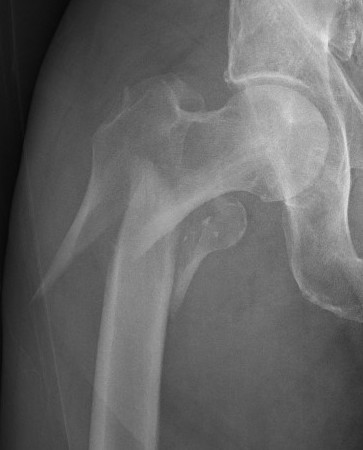

AO classification

32-A3: Short transverse

32-B3: Wedge, fragmented

32-C1: Spiral, complex

Russell-Taylor Classification

Type IA: no extension into piriformis fossa. Simple fracture.

Type IB: IA + comminution

Type IIA: extension through GT into piriformis fossa

Type IIB: IIA + comminution